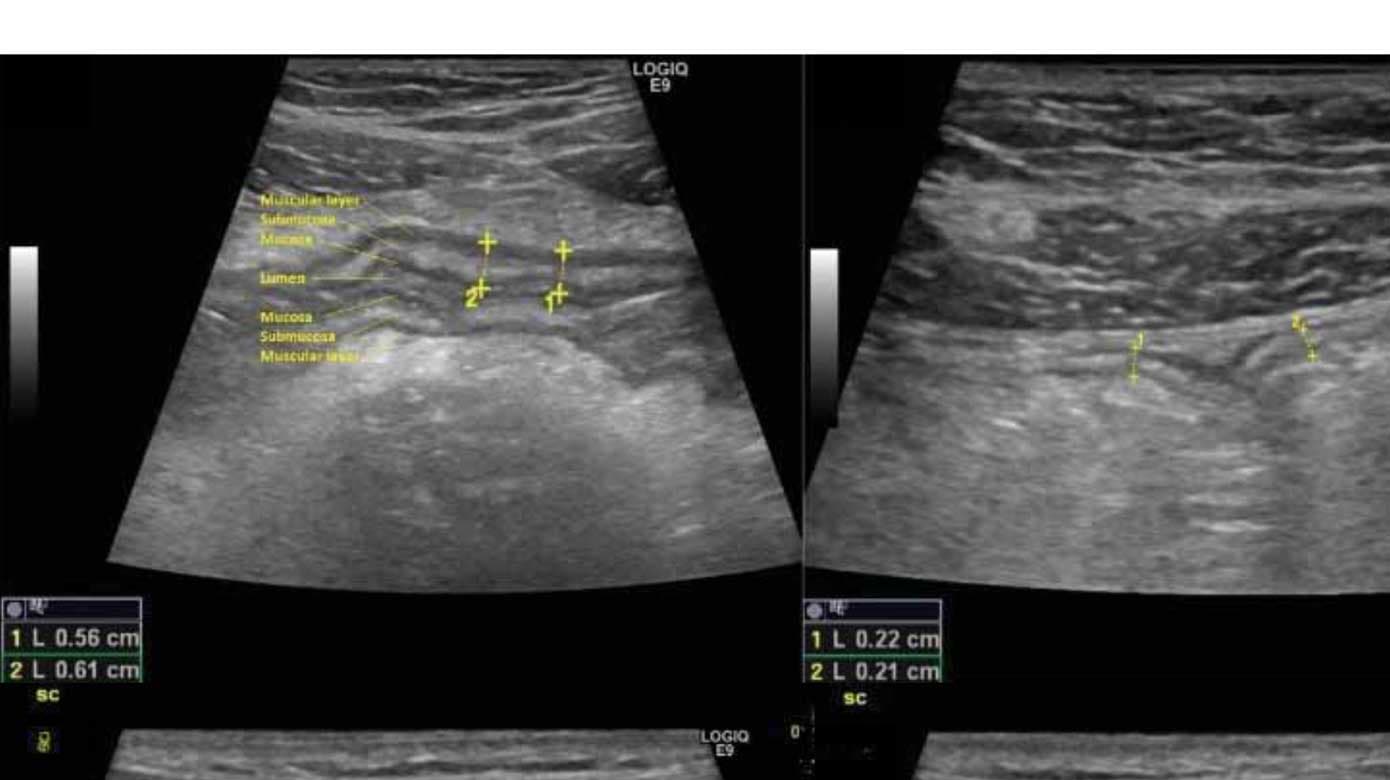

Ved hjælp af TUL identificerer man minimum tre lag i tarmvæggen, og de fremtræder visuelt som »sort-hvid-sort« (Figur 1 A) [17]: Det første hypoekkoiske (dvs. sorte/mørke) lag modsvarer mucosa, mens det næste hyperekkoiske (dvs. hvide/lyse) lag er submucosa. Til sidst ses endnu et hypoekkoisk lag – muscularis propria. Den normale tykkelse af tarmvæggen (bowel wall thickness (BWT)) er < 2,0 mm i både tyk- og tyndtarm (Figur 1 B) [15]. Inflammation vil øge BWT til > 3,0 mm ved både CD og UC (Figur 1 A). Andre mål for inflammation er forstyrret lagdeling i tarmvæggen (dvs. tab af bowel wall stratification) (Figur 1 C + D) samt øgning i CDS (Figur 1 E + F). Endelig ses mesenterial fedtproliferation (Figur 1 C + D) mest udbredt ved CD og forstørrede lymfeknuder i krøset. Stenoser, fistler og abscesser identificeres også ved TUL, og det er muligt at kvantificere en eventuel præstenotisk dilatation [18]. Der er udviklet forskellige aktivitetsscorer, hvoraf International Bowel UltraSound Segmental Activity Score (IBUS-SAS) er valideret til CD [19], mens Milan Ultrasound Criteria (MUC) er valideret til UC [20]. Begge er signifikant korreleret til endoskopiske fund. På den baggrund har vi udviklet en systematisk deskriptiv standardrapport, som indeholder de essentielle informationer og resultater af en TUL ved både CD og UC (Tabel 1).